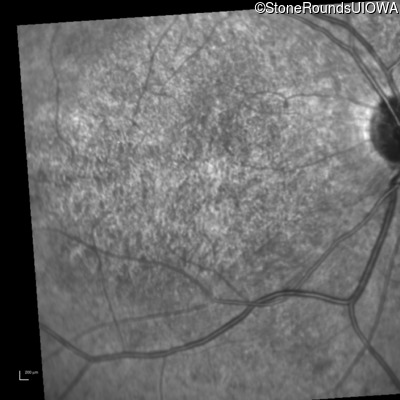

This 14 year old male began having trouble reading before the 1st grade. His parents noticed that he would not look directly at anyone.

| AR Stargardt Disease | ABCA4 | Ala1038Val GCC>GTC / Leu541Pro CTA>CCA | IVS36+3 del4tAAGT | AR |